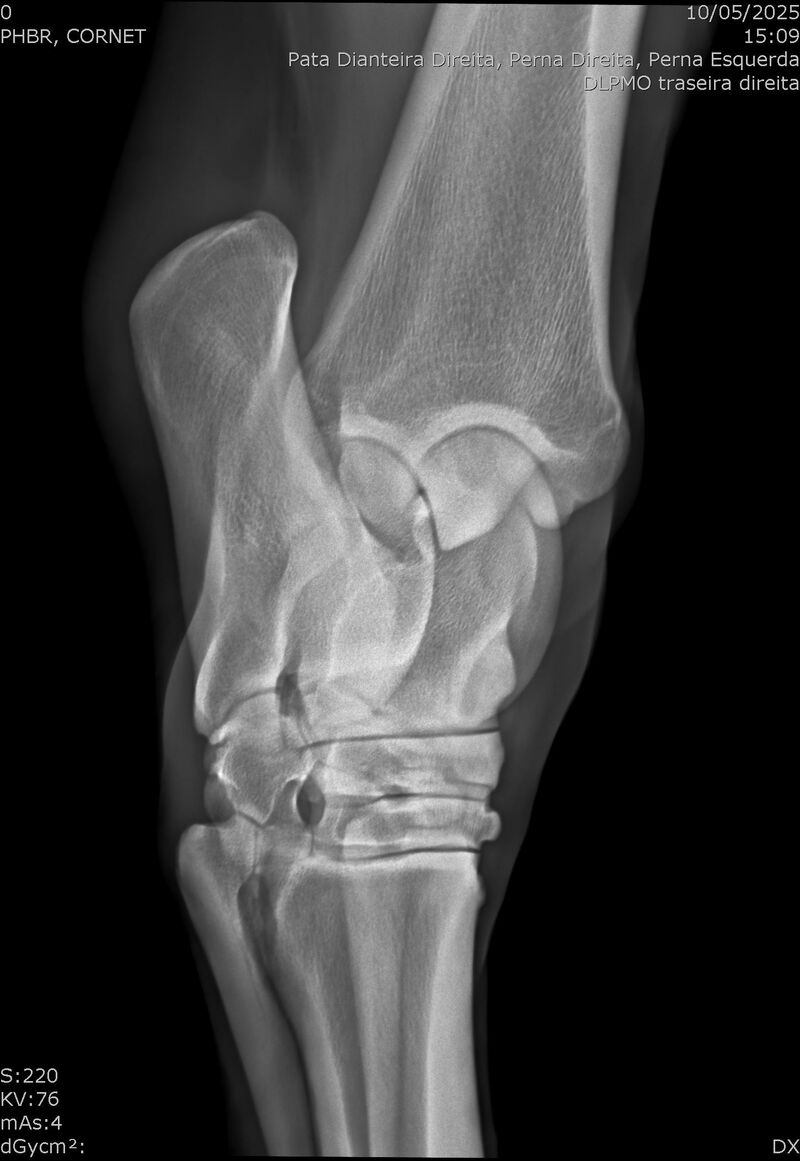

:: RAIOS-X DO LOTE